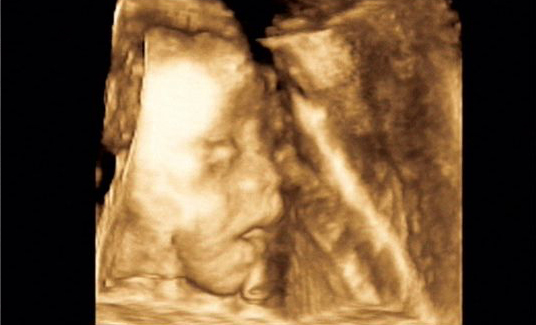

为宝宝留下成长的足迹是每一个准爸妈都想做的事情,准爸妈总是好奇宝宝在肚子里的动态,为了满足准爸妈的好奇心,安徽安琪儿妇产医院引进美国GE—E8四维彩超技术,该技术是目前国际上最先进的四维彩超技术,高清动态的显示胎儿的身体、骨骼、器官的发育情况,并通过高科技技术将宝宝的四维彩超影像刻成光盘,真正的实现零岁动态写真,可供准爸妈随时、反复的观看,为宝宝留下最珍贵的时刻。

四维彩超是目前最先进的一种彩超技术,准妈妈可以清楚的观看到宝宝的动态图像。医生也能够根据四维彩超图了解宝宝的发育情况,是否有唇裂、脑积水、畸形等异常情况,方便医生和孕妇及早的采取应对措施;根据胎儿现今的发育情况及时补充营养,更有助于宝宝的身体发育和智力发育,提高宝宝的健康指数。